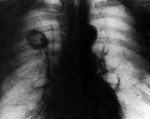

Рентгенологическая картина зависит от формы (узловой, полостной, верхушечной, пневмониеподобной) периферического рака легкого. Наиболее типично выявление неоднородной тени шаровидной формы с неровными контурами в окружении нежного «лучистого венчика»; иногда определяются полости распада. При раке Панкоста нередко обнаруживается деструкция I-III ребер, нижних шейных и верхних грудных позвонков. На бронхограммах видны ампутации мелких бронхов, сужение бронхиальных ветвей. В сложных случаях используется рентгеновская КТ или МРТ легких.